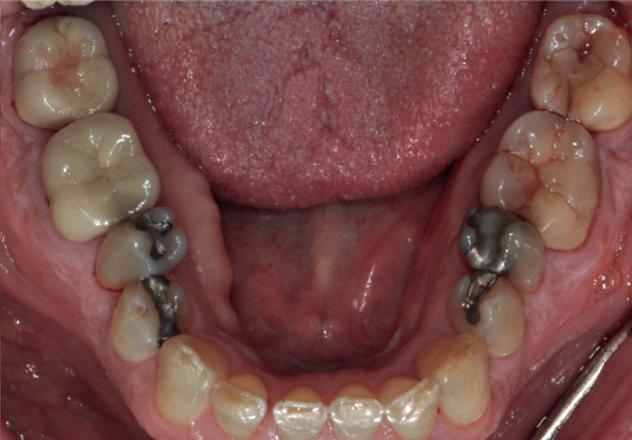

Examinarea parodontală a relevat sângerări generalizate la sondare și adâncimi de sondare de până la 9 mm la molarii maxilari și mandibulari, cu multiple furcații implicate la fiecare molar (fig. 2-7). Prezenta mobilitate multiplă de clasa I la dinții posteriori și de clasa II la dinții nr. 16 și 21 (molarul prim maxilar drept și incisivul central maxilar stâng).

Parodontologul a decis să evalueze dintele nr. 16 în privința PRS, deoarece acesta era molarul cel mai afectat parodontal care urma să fie tratat și menținut pe arcadă (fig. 2 și fig. 8). Acest dinte (molarul prim maxilar drept = scor 1) prezenta adâncimi de sondare de 7 mm (scor 1); trei invazii totale de furcație (scor 3) (mezial [furcație de grad II], vestibular [furcație de grad I] și distal [furcație de grad II]); și mobilitate de clasa II (scor 2). Valoarea totală a PRS pentru dintele 16 a fost de 8, reprezentând un prognostic „rezervat”. Pe baza acestui scor, probabilitatea de a nu pierde niciun dinte din cauza bolii parodontale timp de 15 ani a fost de 81%, iar pentru 30 de ani probabilitatea a fost de doar 56% (fig. 9).

2-4. Imagini înainte de tratament: lateral dreapta (fig. 2), frontal (fig. 3) și lateral stânga (fig. 4). Notă: Molarul prim maxilar drept (dintele 16) (fig. 2) ar fi identificat ca fiind molarul cel mai afectat parodontal care era planificat să fie menținut.

Figurile:

5, 6. Imagini ocluzale înainte de tratament: maxilar (fig. 5) și mandibulă (fig. 6).

7. Rx periapicale înainte de tratament.

8. Rx periapicală a molarului prim maxilar drept (identificat ca fiind molarul cel mai afectat parodontal care era planificat să fie menținut pe arcadă).